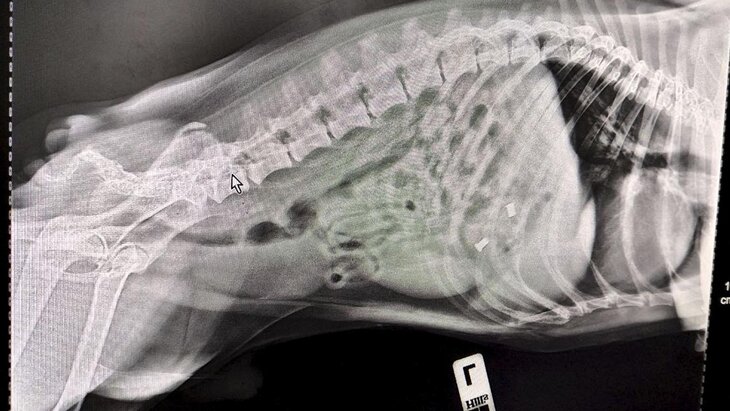

Фото: ГБУ "Мосветобъединение"

"Терапевт Алексей Щукин и УЗ-диагност Елена Сухарева провели УЗИ и рентген, установив, что внутри собаки находится больше чем один предмет. Поскольку Смайла доставили в ветклинику сразу же после происшествия, обошлось без операции. Специалисты вызвали медикаментозную рвоту и удалили предметы из желудка собаки", – отметили в пресс-службе.

В итоге хозяев ждал сюрприз: помимо куска игрушки, врачам удалось извлечь итальянские серьги из муранского стекла, после чего Смайл благополучно отправился домой.